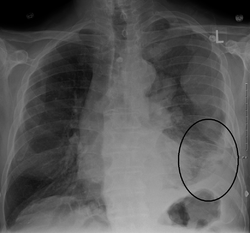

- X-ray - shadowing above the diaphragm, disappearance of the angle above the diaphragm - a side image must also be taken to confirm.